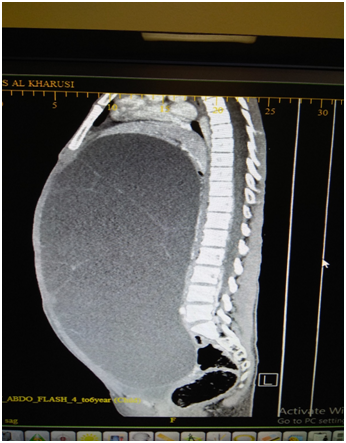

The liver, omentum and retro peritoneum were all normal. A thorough peritoneal lavage was done before closure, taking care to send the lavage returns for cytology- that was later reported as normal, with no malignant cells. Patient made an uneventful recovery and was discharged on the 3rd day. We received the final histology as follows. The cyst shows features of a Mucinous Cyst adenoma with Borderline Malignancy. No evidence invasion of the wall and no tumor of the external surface. Tubes showed evidence of salpingitis isthmica nodosa. FIGO classification Stage 1A (Figure 4).

Figure 4 Histology low and high power field showing papillaroid mucosa lined by mucinous lining epithelium which show stratification and atypia.